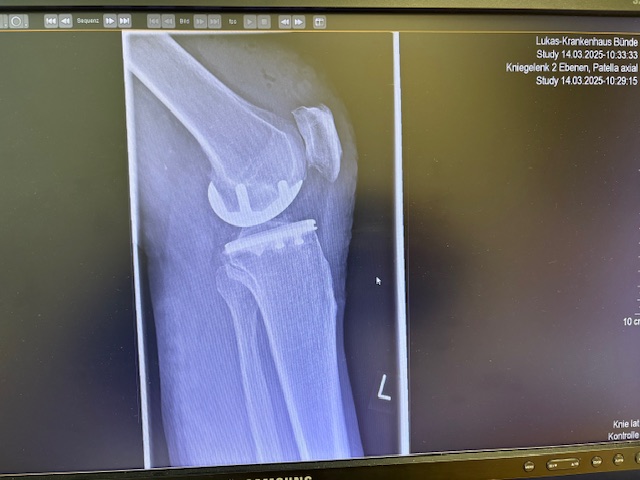

Ο ακτινολογικός έλεγχος (ακτινογραφίες/μαγνητική τομογραφία) ανέδειξε προχωρημένη οστεοαρθρίτιδα του έσω κονδύλου, με πλήρη διατήρηση του έξω διαμερίσματος και της επιγονατιδομηριαίας άρθρωσης. Με βάση αυτά τα ευρήματα, ο ασθενής ήταν ιδανικός υποψήφιος για μερική (μονοκονδυλική) αρθροπλαστική γόνατος.

Η επέμβαση πραγματοποιήθηκε με ελάχιστα επεμβατική προσπέλαση και τοποθέτηση πρόθεσης μόνο στον έσω μηροκνημιαίο διαμέρισμα του γόνατος.

Η ακριβής προσαρμογή του εμφυτεύματος επιβεβαιώθηκε διεγχειρητικά, εξασφαλίζοντας σταθερότητα και φυσική κίνηση της άρθρωσης.

Στον ασθενή τα εμφυτεύματα που χρησιμοποιήθηκαν είναι της εταιρείας Zimmer-Biomet Persona Μηριαίο μέγεθος 6, κνημιαίο μέγεθος Η και ενθέμα (inlay) Η li. 8mm.